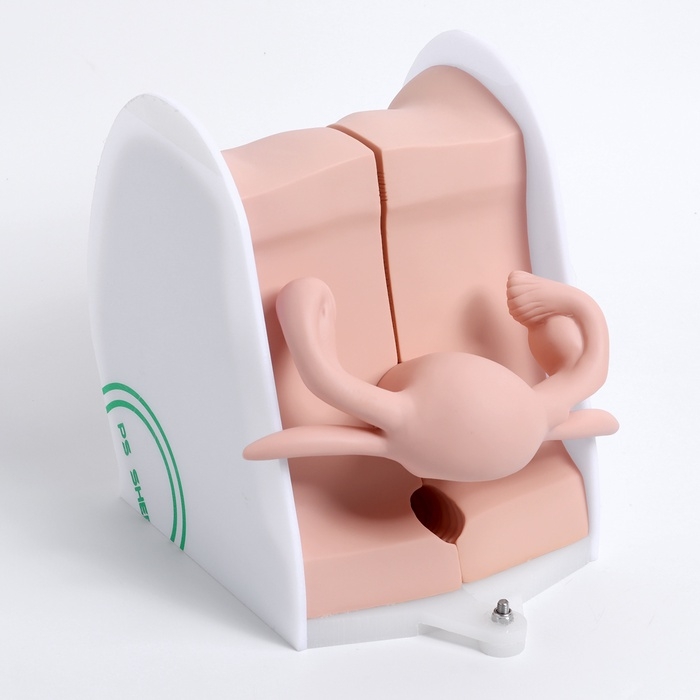

Анатомические модели

ЕКБ 167

No Brand, артикул: 7072352